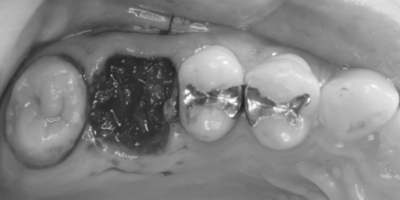

右上6抜歯後

右上の抜歯後の治癒を待つため、抜歯の1ヶ月後に移植を行うこととした。

抜歯1ヶ月後

移植手術後

右上6抜歯1ヶ月後、移植手術を行った。

右下8を抜歯し右上6部に移植、縫合糸で固定した。

移植手術後、治癒に異常を認めなかったため、移植2週間後に根管治療を行った。